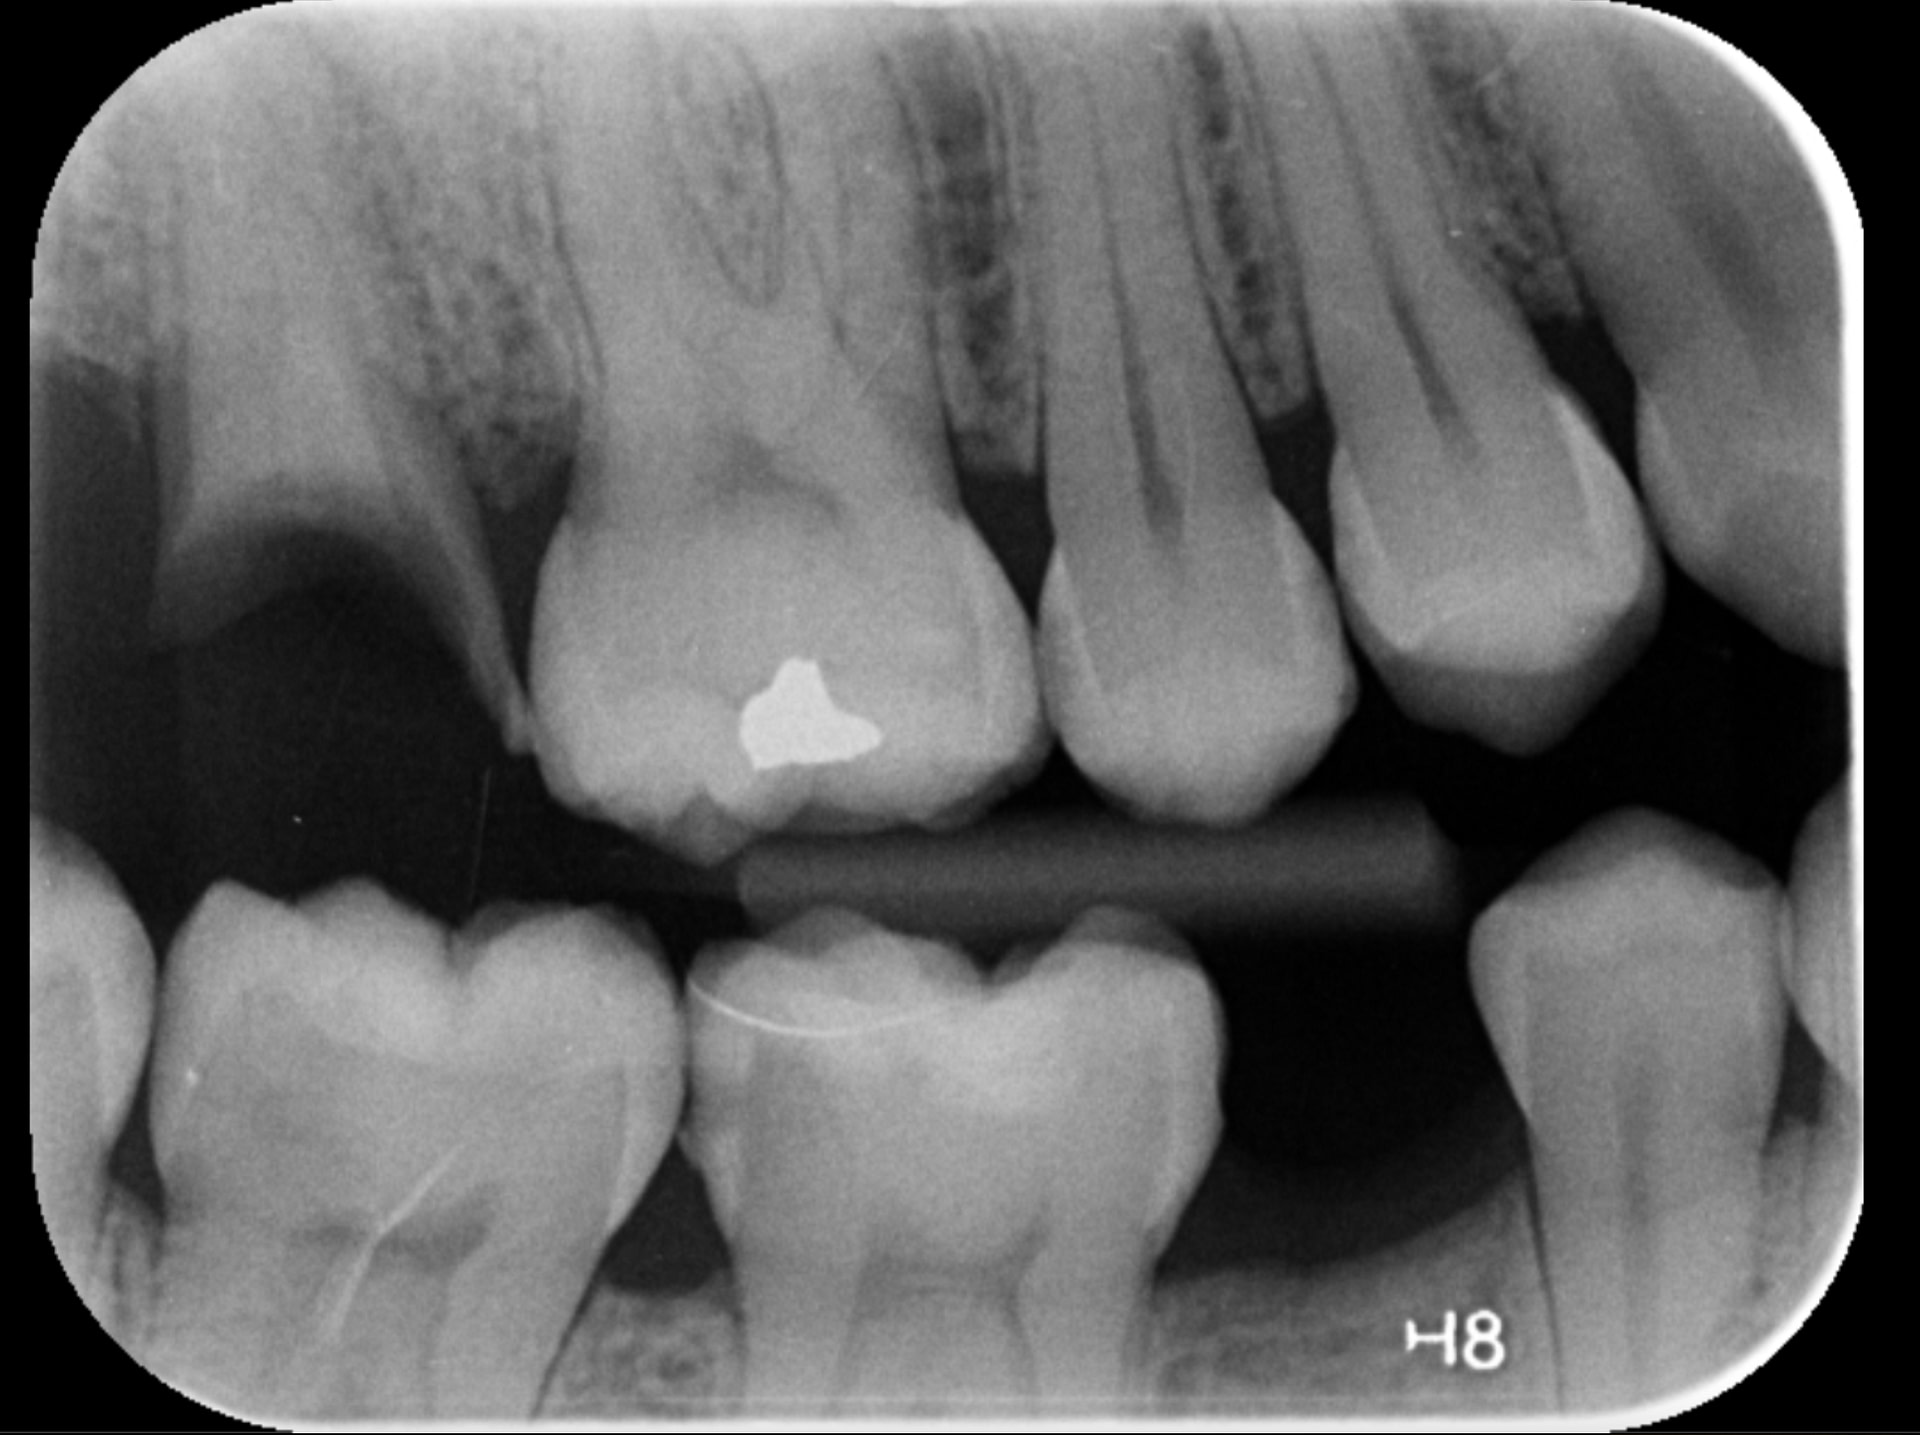

Caries Detection

The best for last and arguably the most well-thought-out feature. Especially with the tooth segmentation mode, which makes it easier for patients to understand their diagnosis and treatment plans.

The system uses two shades of pink to indicate potential caries:

- Light pink: Incipient caries (100% in enamel) - we will often review

- Darker magenta: Caries extending into dentin - we need to restore

The system even provides a percentage breakdown of enamel vs. dentin involvement. I have been blown away by its accuracy while using it, and it makes something that feels quite subjective (reading shades of grey) into a science.

This feature is very useful for patient education and deciding between preventive measures and restorative treatment. However, remember that radiographic evidence alone is not always sufficient for a definitive caries diagnosis.